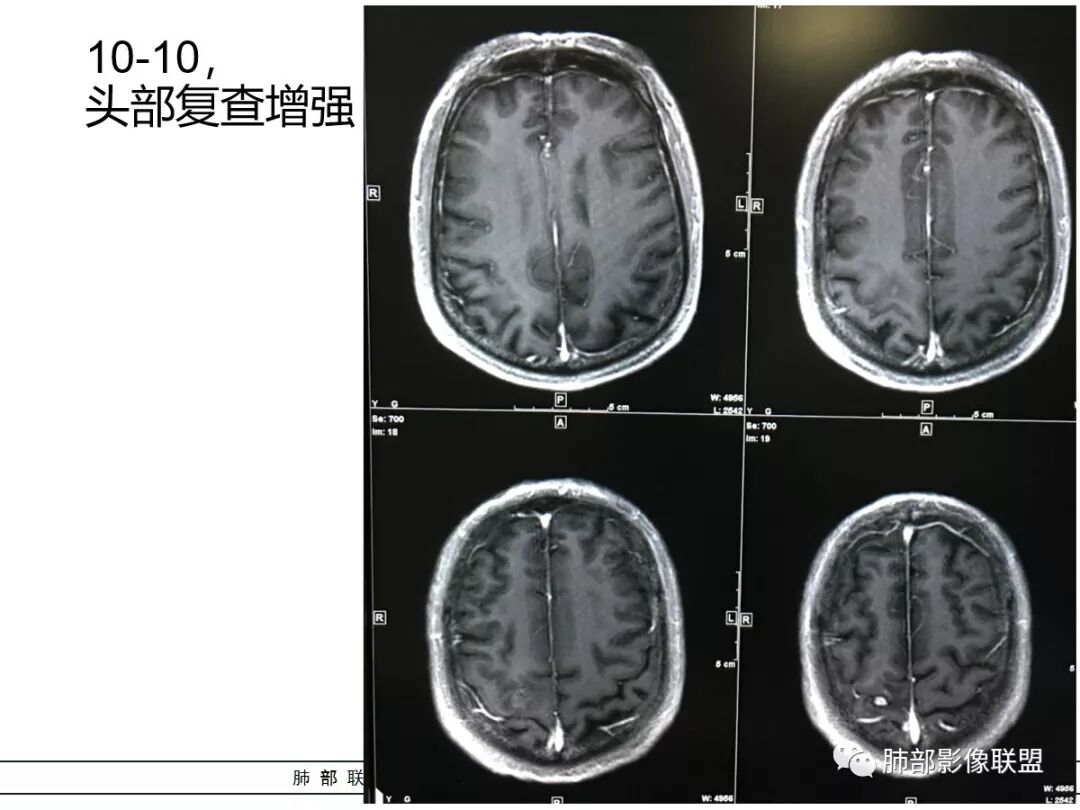

右肺下叶团块状密度增高影,边缘模糊,其内见液性低密度影,多发小气泡影及充气支气管征,考虑肺脓肿。颅内双侧顶叶长T2长T2病灶,周围水肿,DWI高信号,增强扫描囊壁环形强化,囊壁钙化,周围水肿,考虑脑脓肿。患者长期接触垃圾,什么菌都有,肺、脑脓肿,考虑肺克。再有肝脓肿就更支持了。

右肺下叶背段实变,广基底,糊墙,长轴与平行胸膜,周围有晕,支气管进入堵塞,可见低密度坏死及小空泡。颅内多发环形强化灶,符合脑脓肿三层结构,结合临床,考虑:感染性病变,隐球菌?鉴别肺克。

颅内多发类圆形等或长T1长T2信号,周围见少量环形水肿带,考虑多发脓肿,不符合转移瘤表现。综合肺脑脓肿,考虑隐球菌可能

右肺下叶见不规则软组织影,边缘不清,内夹杂气体,背段支气管未见明显阻断,增强扫描下叶病灶内见类圆形低强化区,其边缘光滑,见低强化区壁,颅脑左侧枕叶及双侧顶叶见多发长T1长T2信号,T2高信号内见类圆形异常信号,壁呈低信号,DWI环形壁未弥散受限,内容物弥散受限,周围为水肿区,增强扫描呈多发环形强化,考虑血源型感染,颅内及右肺下叶脓肿形成

3.脑内多发混杂信号病灶,显著长T1、显著长T2信号为主。注意TW1及TW2均显示环形等密度影(这在转移瘤是非常罕见的)且出现相应的环形强化。中央液化区DW扩散受限以及周边广泛水肿等,都符合典型多发脑脓肿改变。

4.脓腔较大,也更符合细菌感染。(脑内结核、隐球菌及奴卡菌感染病灶通常不易有如此大范围)

综上患者符合肺脓肿及脑脓肿诊断,病原菌以肺炎克雷伯杆菌等感染可能性较大